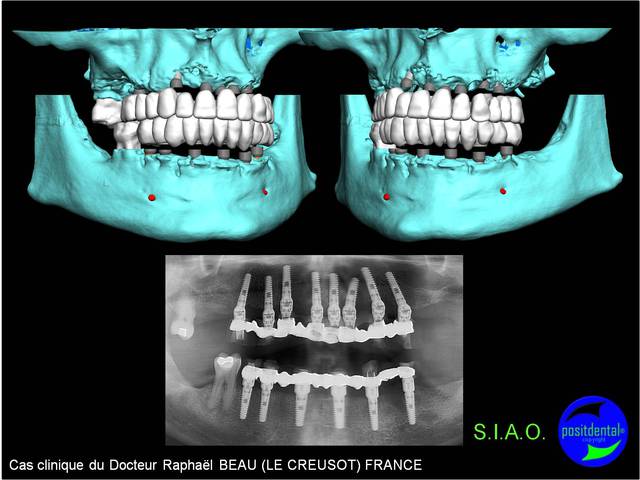

pano de contrôle à 10 jours post op...

tout va bien, aucune douleur, juste une petite correction de hauteur des incisives sup pour la phonation (les F)...;-)